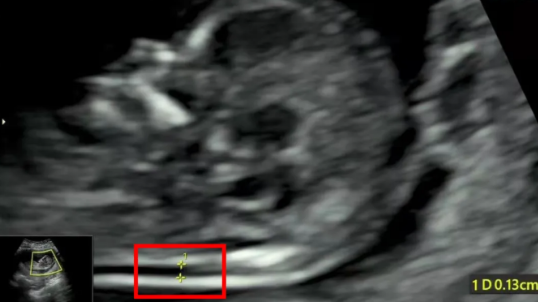

NT增厚的胎儿,是否一定有问题

NT增厚越明显,胎儿异常机会就越高,异常程度也会越严重。一般正常的NT厚度不能大于3mm,超过3mm表示NT增厚,存在异常可能。

NT异常增厚的主要原因,可能与胎儿染色体异常有关,比较常见的有2 1-三体、18-三体、13-三体综合征等;也可能是胎儿结构畸形,比如说心脏、骨骼系统发育的异常,但是相对于染色体异常来说,结构畸形或其他原因导致NT增厚占比较小。

另外,还有很多宝宝NT增厚是找不到原因的,如果宝宝染色体是正常的、结构是正常的,那么增厚的NT值会随着孕周的增长慢慢消失、恢复正常,须重视产检复查。